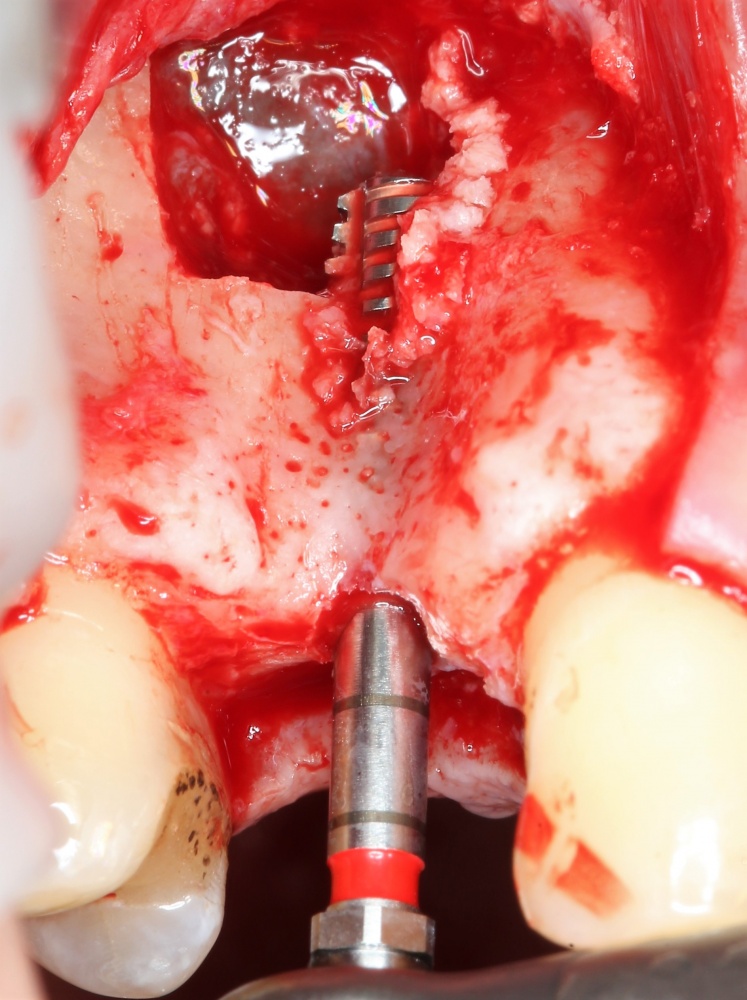

Прежде, чем приступить к аугментации (пластике) лунок зубов, мы подготовили лунки для имплантатов. В таких клинических случаях нет необходимости в использовании шаблона. Вместо этого, мы применяем общепринятые правила позиционирования и соблюдаем рекомендации производителя по хирургическому протоколу:

В процессе ирригации лунки промываются, что позволило нам еще раз подтвердить ранее сделанные выводы. С помощью аналогов имплантатов, входящих в хирургический набор Xive, мы проверили возможность стабилизации имплантатов в будущих лунках. Исходя из правил подбора и позиционирования имплантатов (я очень рекомендую почитать об этом здесь>>) мы остановились на Xive S диаметром 3,4 мм и длиной 13 мм.

Затем уложили ксенографт. Особенностями Bio-Oss Collagen являются удобство адаптации, устойчивость к вымыванию и выдавливанию, поэтому мы просто уложили полученные ранее пирамидки вестибулярно относительно будущего имплантата, после чего прижали их с помощью уже упоминавшихся аналогов имплантата, входящих в хирургический набор имплантационной системы Xive (кстати, при работе с другими имплантационными системами для паковки графта в лунке можно использовать круглые остеотомы для синуслифтинга).

В совокупности, аугментация лунок перед установкой имплантатов занимает около 20 минут — и это самый долгий из всех хирургических этапов лечения.

Установка имплантатов

По ряду уже упомянутых выше причин, для решения этой клинической задачи мы выбрали имплантаты Xive. Лунки для них мы уже приготовили. возможную первичную стабильность оценили. Имплантаты мы установили с усилием чуть больше 15-20 Нсм — такого крутящего момента более, чем достаточно, особенно если учесть, что временные коронки будут соединяться между собой.